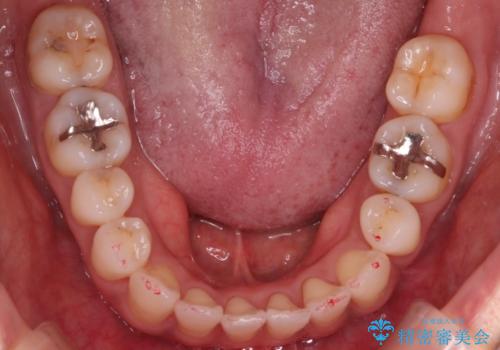

【審美装置】抜歯の本数最小限で行った矯正治療

- 治療計画

- 全体のがたつきを主訴に来院されました。4番目の歯を4本抜歯も検討しましたが、口元が下がりすぎてしまうリスクと2番目の転位うが著しく並べるのにかかる期間を考慮し、変則的な抜歯をし、並べる計画を立てました。

抜歯矯正のため2年はかかってしまいましたが、きれいに並び患者様にも満足頂きました。